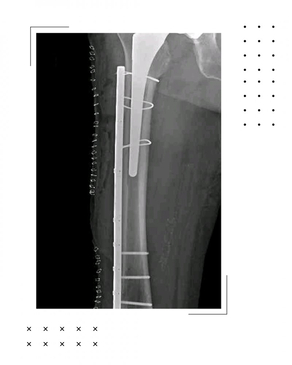

Dr. Rodrigo Aguirre Rojas is the best Orthopedic Surgeon in San Jose del Cabo, Mexico. Book your consultation for Hip and Knee Replacements in Los Cabos, Mexico at PlacidWay. Emergencies like Fractures and Dislocations are also evaluated and treated